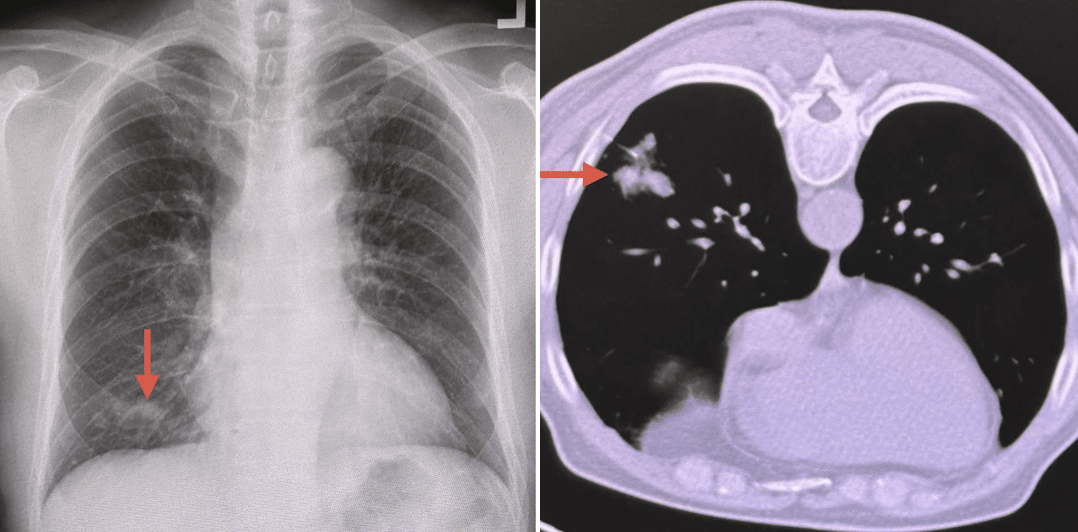

เมื่อทำการตรวจร่างกายอย่างละเอียด ฟังเสียงปอดดูปกติ แต่ผลการเอกซเรย์กลับพบความผิดปกติ คือมี ฝ้าขาวเล็กน้อยที่ปอดข้างขวาด้านล่าง เมื่อทำคอมพิวเตอร์สแกนปอด (CT Scan) ยืนยันรอยฝ้าขาวดังกล่าว แพทย์จึงดำเนินการสืบค้นต่อด้วยการส่องกล้องเข้าไปดูในหลอดลม แต่ไม่พบสิ่งผิดปกติ

ทีมแพทย์ตัดสินใจส่งน้ำล้างหลอดลมไปเพาะเชื้อ พบว่าเป็นเชื้อรา คริปโตค็อกคัส (Cryptococcus) และเพื่อความแน่ชัด จึงใช้เข็มเจาะปอดบริเวณที่เป็นฝ้าขาวเพื่อนำชิ้นเนื้อไปตรวจพยาธิวิทยา ผลยืนยันตรงกันว่าพบเชื้อราตัวเดียวกัน (ผลตรวจเลือดหาแอนติเจนและ HIV เป็นลบ)

แพทย์วินิจฉัยว่าเป็น โรคปอดอักเสบจากติดเชื้อราคริปโตค็อกคัส จึงให้การรักษาด้วยยาต้านเชื้อรา Fluconazole นาน 6 เดือน จนกระทั่งเอกซเรย์ติดตามผลพบว่าฝ้าในปอดหายเป็นปกติ